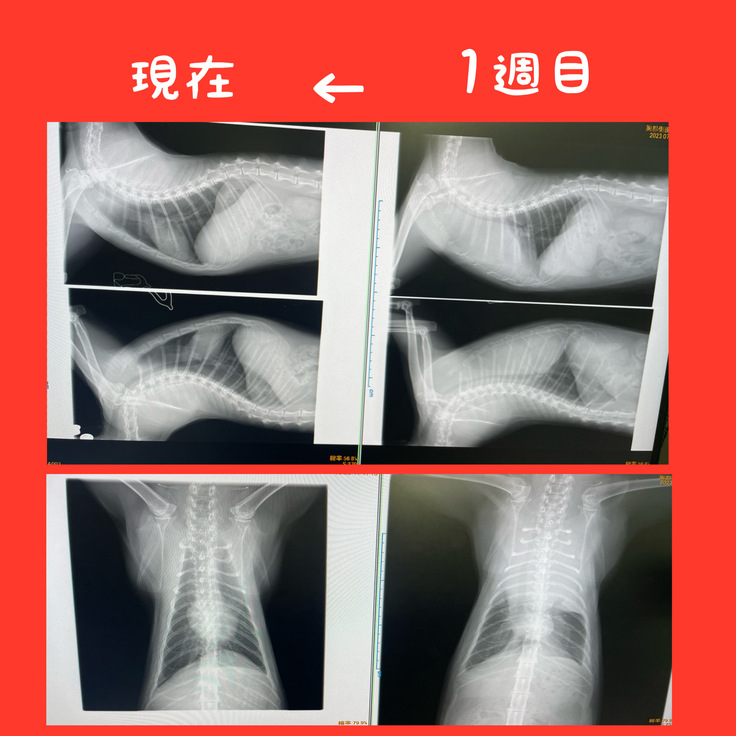

今ぐらいに再発が心配されるみたいですがそれもレントゲンでは確認されなかったので

一安心です。

お腹の中が腫瘍てー覆われることによって

骨や呼吸する器官が圧迫されていたのが

今は骨が透き通って見えてます😭

それだけ腫瘍が小さくなっている証拠です!